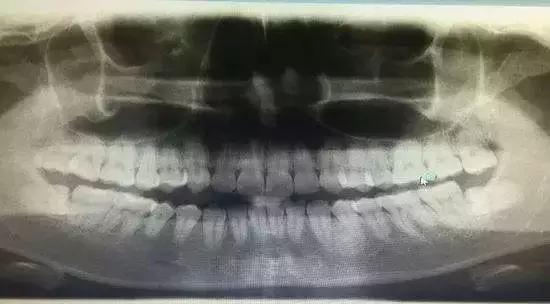

Step2 拍牙片

一般拔牙前,医生会给你拍个牙片。

拍牙片的目的是为了看清楚牙根的生长情况。比如:智齿,他们身姿千变万化。了解清楚智齿的生长的情况,才会在拔牙的时候合理用力,避免伤害邻牙。